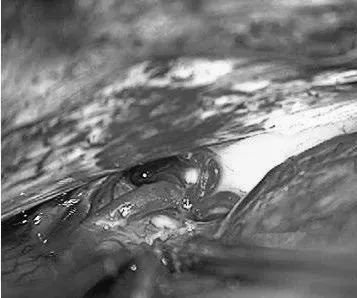

患者案例1:该患者为47岁男性,表现为合并胼胝体AVM的较大胼周动脉瘤破裂后昏迷(补充Spetzler-Martin分级为6级:S2V1E0/A3B0C0)。

手术步骤图解

他紧急行半侧颅骨切除术,随后血管造影显示右侧动脉瘤,AVM由双侧PcaA供血,引流向前MedFrV和SplenV【左侧ICA像,(a)前后位(b)侧位】(c)首先通过双侧开颅并排夹闭动脉瘤(鼻朝右,中线呈水平,重力牵开右侧额叶),然后切开动脉瘤使之缩小。